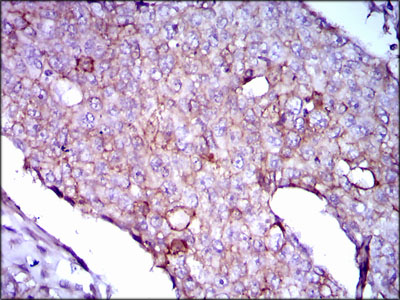

Immunohistochemical analysis of paraffin-embedded human liver cancer tissue using anti- Lipoprotein a antibody. Counter stained with hematoxylin.

Immunohistochemical analysis of paraffin-embedded human breast cancer tissue using anti- Lipoprotein a antibody. Counter stained with hematoxylin.

Immunohistochemical analysis of paraffin-embedded human rectum cancer tissue using anti- Lipoprotein a antibody. Counter stained with hematoxylin.